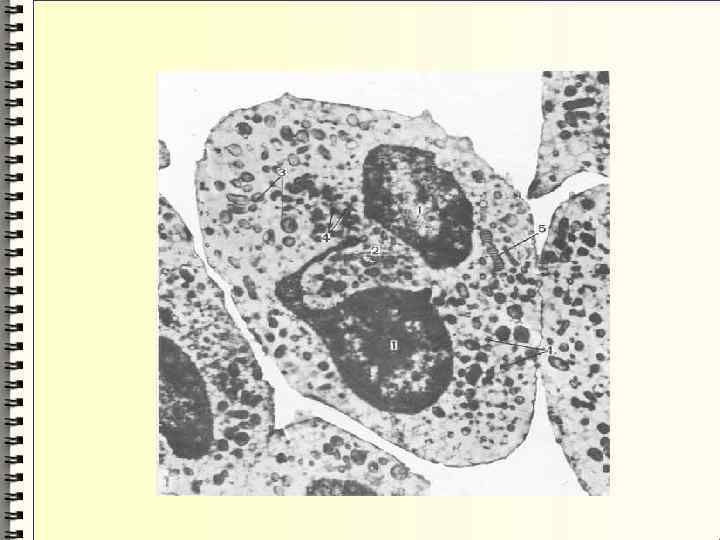

Микроскопия мочи Объектив Микроскопию препарата начинают с малого увеличения микроскопа окуляр х10, объектив х10 для общего обзора. При этом легче обнаруживаются цилиндры, скопления клеток, крупные кристаллы. Затем для детального изучения препарата переходят на большое увеличение микроскопа окуляр х10, объектив х40. Конденсор при этом опускают и суживают диафрагму.

Осадки мочи подразделяются на: Организованные клеточные элементы цилиндры бактерии Неорганизованные разнообразные мочевые соли

Цилиндры Образуются в почечных канальцах Представляют собой слепки канальцев из свернувшегося белка и клеточных элементов Имеют цилиндрическую иногда изогнутую форму и разную величину Концицилиндров могут быть тупыми, обломанными или закругленными

цилиндры белковые клеточные (гиалиновые (эпителиальные и лейкоцитарные восковидные) эритроцитарные)